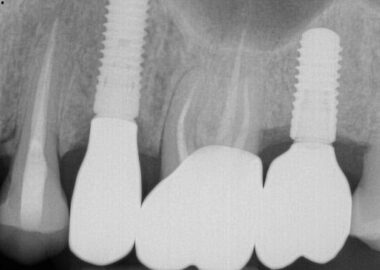

The patient was referred by Dr. P. and Dr. L. for retrieval of a fractured abutment screw in a Straumann 4.1 BL implant in the #15 site. This implant had been in function since 2015. The abutment screw fractured on initial placement when Dr. L. applied additional torque to the screw when the crown still felt loose after the initial placement. This abutment and crown combination was manufactured by G. Labs as this new restoration was replacing an existing crown and abutment which reportedly had an open contact issue. The original crown had been manufactured by G.Labs so there was a warrantee issue involved, which pushed the decision to have G.Labs remanufacture the case. Initially after the fracture, the patient was referred to Dr. P., a periodontist in San Diego, for retrieval help. The patient reported that after approximately 1.5 hours without success, Dr. P. decided to abandon the effort and refer the patient here.

Following a detailed discussion of the retrieval algorithm, the site was infiltrated, and a conservative exposure was made of the implant top, avoiding the existing sutures from the prior recent flap procedure. The initial preoperative photo shows the extent of the previous effort, where a slot strategy was attempted into the top of the screw fragment but also into the top aspect of implant adjacent to the start of the implant threads. This screw fragment was residing slightly below the first implant thread and was non-mobile so in my treatment algorithm it was classified as a Type IV case which required a concentric mobilization technique. The center of the screw fragment was identified and spotted with a custom prototype guide and specific custom spotting drill and modified until it was concentric enough to safely proceed with the actual drilling. The drilling protocol was initiated at .8mm and was taken completely through the fragment. A modified ratchet drive easy-out type screw extractor was then engaged and with considerable force the fragment was delivered intact. A M1.6 tap was chased through the treads to ensure continuity and a Straumann healing abutment was placed finger tight. The patient was referred back to Dr. L. to continue with the restorative phase. Even though there was prior damage to the implant from the original recovery effort, going forward, the prognosis for this implant remains unchanged secondary to this event or recovery efforts as the damage occurred in essentially a non-critical area between the critical top indexing and the lower threaded areas. The patient was very pleased with the successful outcome.

So why did this screw fail? Examination of the crown lead to the answer. The initial clue was the looseness that was felt after initial torqueing. As the crown was present at this appointment, it was tried onto an RC analog and found to be very loose fitting even though the custom prototype RC drill guide fit the implant very well, confirming the RC implant interface. However, when tried onto an NC analog it fit with precision. Obviously, this was an error with the wrong size abutment interface. As both NC and RC platforms utilize the same M1.6 diameter screw, it is possible to thread in an NC screw into an RC implant. Unfortunately, that’s where the compatibility ends. The NC platform has a smaller crossfit connection and the NC abutment screw actually bottoms out before the head of the screw engages the screw seat. This allows all of the total torque placed on the screw to become thread torque with none bleeding off in the screw head seat. The screw fragment is essentially driven and wedged into the bottom of the implant wedging between the bottom and the last implant thread at full torque before fracture. This is why retrieving a fragment like this one often results in having to recover the screw fragment in pieces depending on the amount of torque the recovery tools can deliver. We were definitely fortunate to recover this fragment in one piece, but we were also prepared to proceed to a total drill out with the protocol we were following.